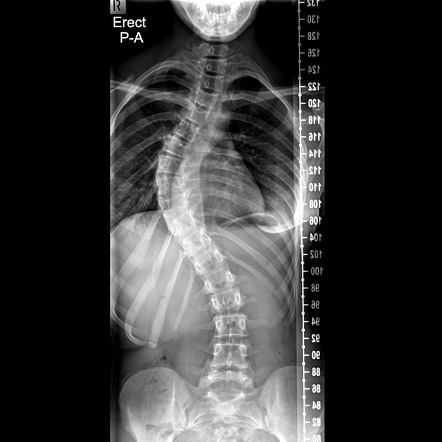

- الفحص السريري

- تقييم حركة الجسم

- الأشعة